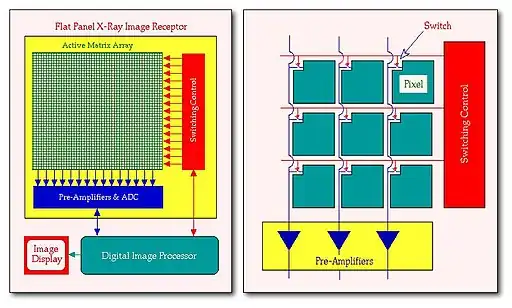

- Considerable research has been conducted in recent years into the development of flat panel image receptors for digital radiography. This research has extended from the development of active-matrix liquid-crystal flat panel displays (AMLCDs) for application in, for example, portable computers. The underlying technology of AMLCDs is a large area integrated circuit called an active matrix array which consists of many millions of identical semiconductor elements deposited on a substrate material. An intensifying screen or a photoconductor coupled to such an active matrix array forms the basis of flat panel X-ray image receptors.

- Such a receptor is illustrated in the following figure, where the active matrix array and associated electronic circuitry is mounted in a device which replaces the X-ray cassette in screen-film radiography:

- Array sizes of up to 43 cm x 43 cm have been constructed with more than 9 million pixels (pixel size ~150 μm). Operation of the array is controlled by a digital image processor which also stores and displays the resultant images.

- The operation is illustrated in more detail in the right panel of the above figure. Each pixel of the array has a switch (typically made from a thin film transistor) which is connected to switching control circuitry in a manner which allows all switches in a row of the array to be operated simultaneously. The output from each pixel is connected in columns with individual pre-amplifiers.

- All switches are kept in the off position during the X-ray exposure. Following the exposure, the switches in the first row are turned on and the signal from each pixel is amplified by the pre-amplifiers, digitised in an analogue-to-digital converter (ADC) and stored in the image memory of the digital image processor. These switches are then turned off and the switches in the second row are turned on to acquire signals from the second row of pixels. This process is repeated for the whole array so that an image is acquired in a sequential, line-by-line manner.